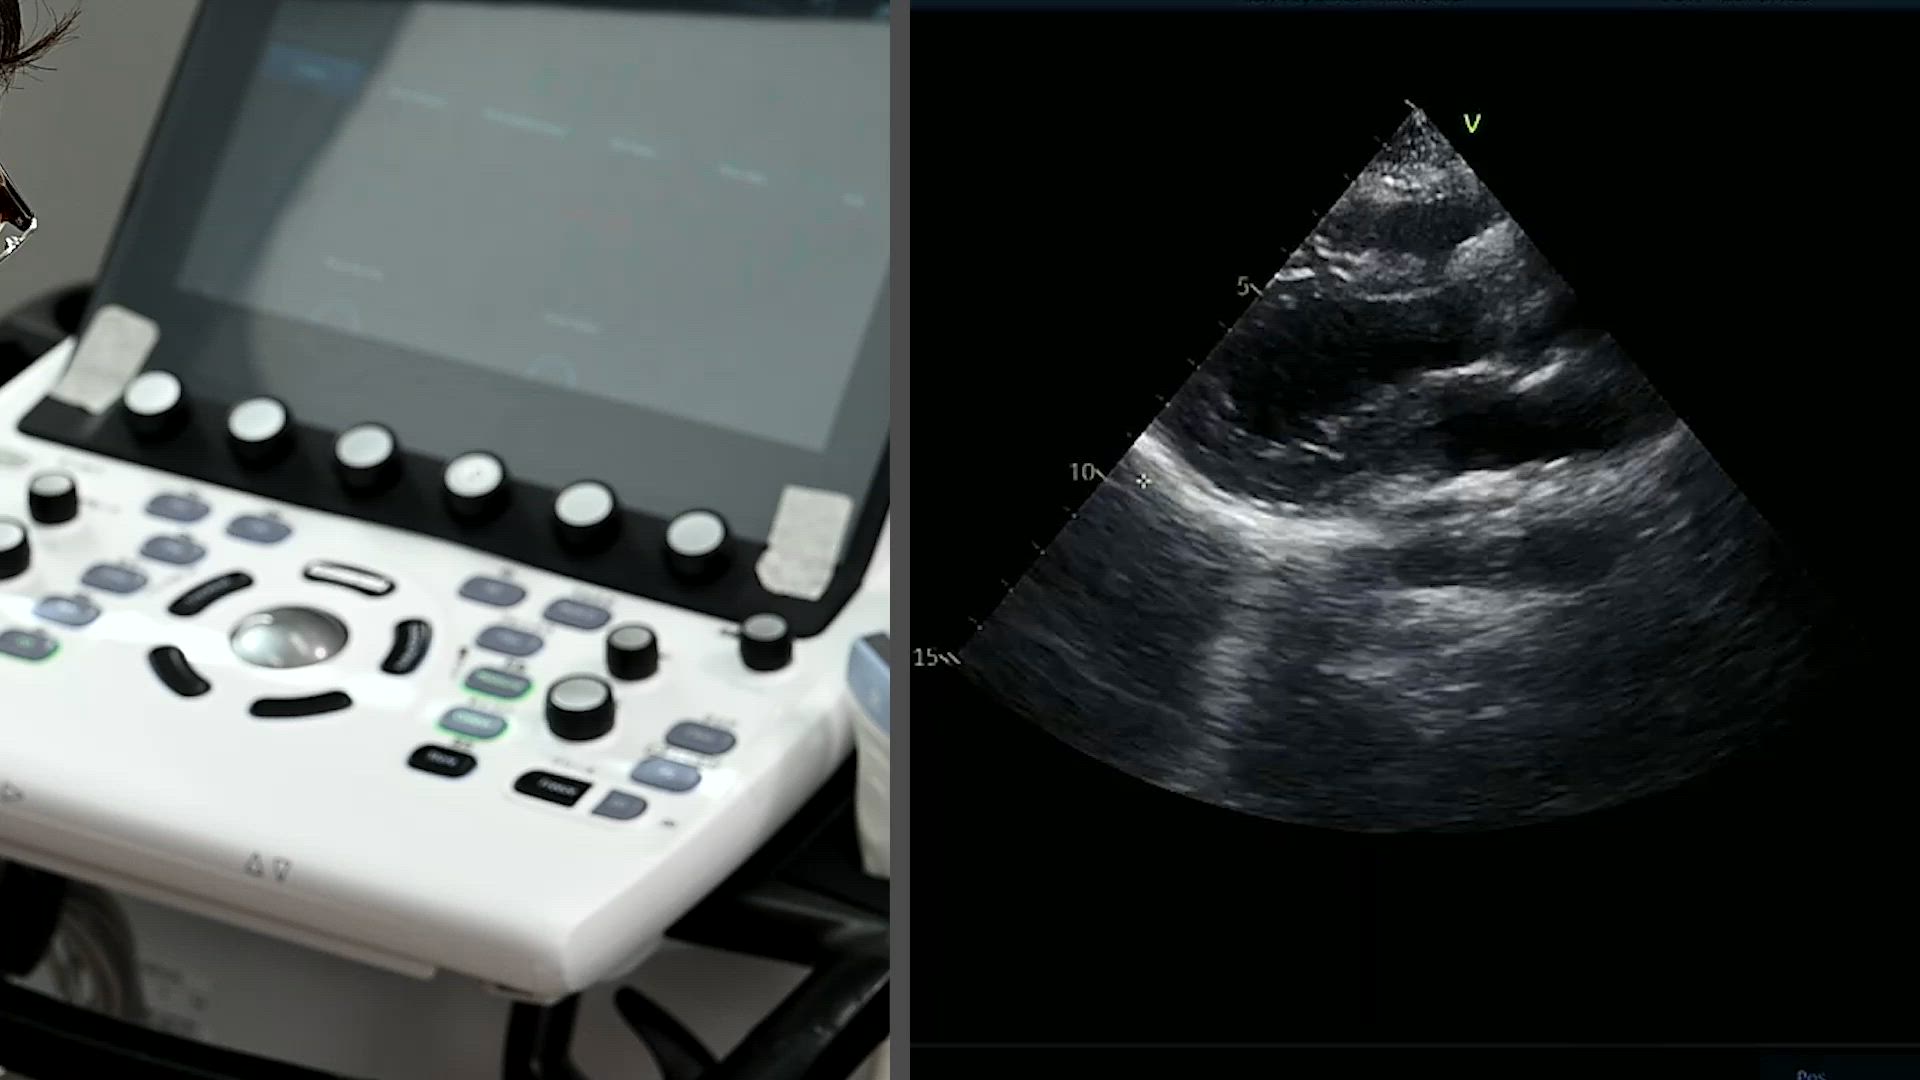

心臓POCUS(心臓超音波検査)by エコーボーイズ

プローブの操作方法

検査を始めるための準備

デプス・ゲインの調整

心窩部アプローチ

傍胸骨アプローチ

傍胸骨アプローチ(左側臥位)

心尖部アプローチ(左側臥位)

Basic FoCUS復習

06:01

Basic FoCUS復習(対面)

advanced FoCUSレクチャー